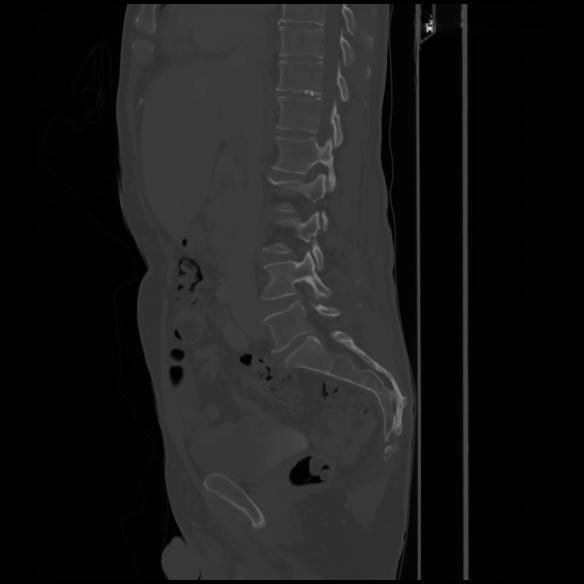

7 CUERPO,CE,Sagittal,3.000,CUERPO,Sagittal,